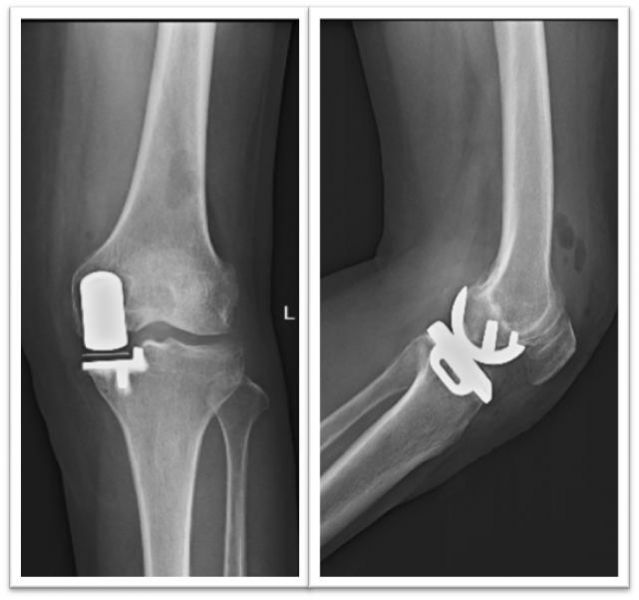

术前膝关节正侧位片

术后膝关节正侧位片